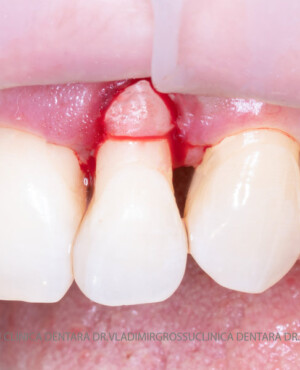

Adiția de gingie (gingivoplastia)

Aditia gingivală este o procedură chirurgicală ce corectează diverse probleme estetice și funcționale, cum ar fi recesiunea gingivală. În implantologia modernă, aditia de țesut moale este utilizată aproape în fiecare intervenție de inserție a implantului dentar pentru a asigura un aspect estetic natural și o bună integrare a implantului în cavitatea bucală.